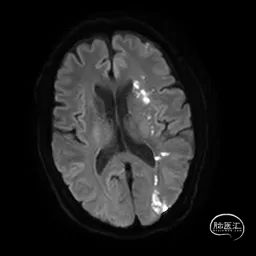

术前影像学检查结果

术中3D证实明确左侧大脑中动脉重度狭窄,完成测量并选取治疗角度。

基于多项研究,目前对于颅内动脉狭窄的介入诊疗临床上偏于谨慎对待,对于单纯的狭窄而没有症状多倾向于定期随访保守治疗,但是根据我院单中心经验,责任病变(有临床症状、核磁证实新发梗死),明确的低灌注以及核磁证实的穿支事件风险较低时,可以结合患者的治疗意愿进行介入诊疗,该例患者即是基于以上的原则进行了相关治疗。